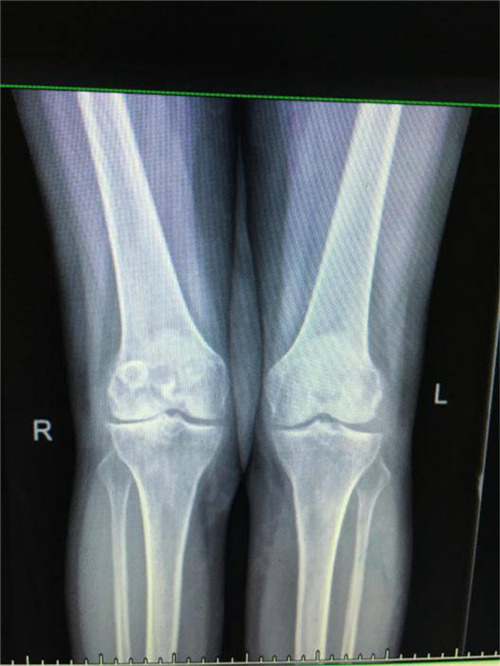

得知郴州市第四人民医院骨科掌握了这一手术技术,便前来就诊。谭主任接诊到该患者后,对其进行了详细的体魄检查,发现其左膝关节僵直,屈伸活动不能,负重时膝关节疼痛明显加重,膝关节X线片提示膝关节退变严重,关节间隙明显变窄,并有游离体形成,诊断为左膝关节重度骨关节炎并关节僵直,有明确的膝关节置换手术指征。

术前X线